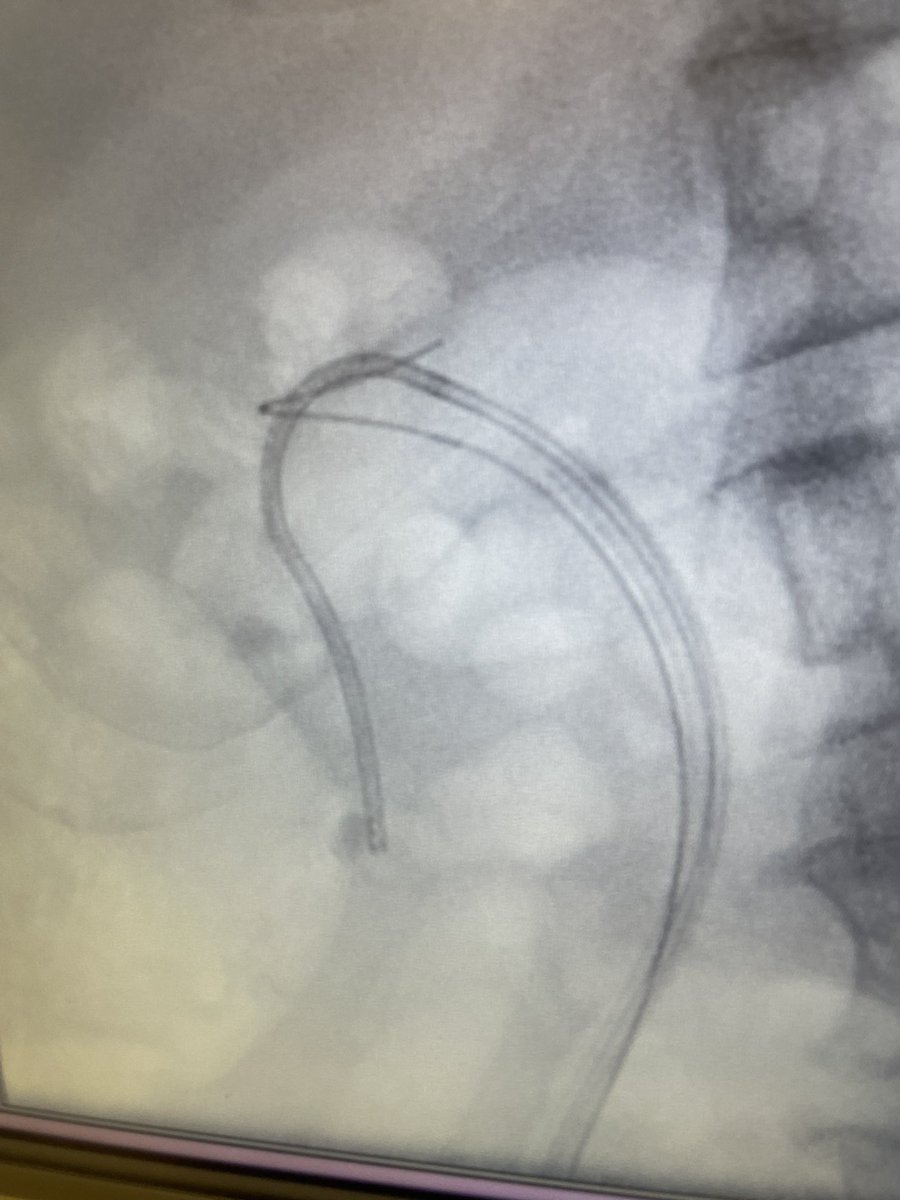

We had the opportunity to try out the flexible tip ClearPetra access sheath @ClearpetraL Truely amazed and firmly believe that it is the future of stone surgery. @FrimleyUrology @SimonBott6 @brett_lamper